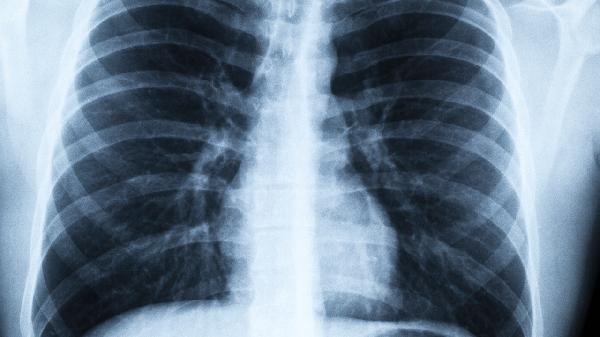

1.低剂量螺旋CT:肺癌筛查的“金标准”

低剂量螺旋CT是目前公认的肺癌筛查“金标准”,尤其适合早期肺癌的发现。它的优势在于辐射剂量低,但成像清晰,能够发现小到几毫米的肺部结节。对于长期吸烟、有肺癌家族史、长期接触二手烟或空气污染的人群来说,这项检查简直就是“救命稻草”。数据显示,低剂量螺旋CT能够将肺癌死亡率降低20%以上,可见其重要性。如果你属于高风险人群,建议每年做一次,早发现早治疗,别让肺癌有机可乘。